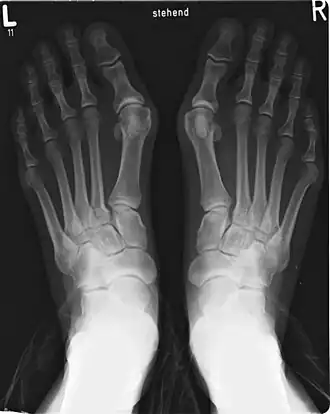

El dedo gordo es el primer dedo y el más interno del pie, aunque existen variaciones de la fórmula digital. En el pie normal o «pie egipcio» (69 % de la población) es de mayor longitud y grosor que los demás. Se denomina «pie griego» a aquel en el que el dedo segundo es de mayor longitud que el dedo gordo (10-22 % de la población) y pie cuadrado o «polinesio», a aquel en el que los primeros tres dedos son iguales (9 % de la población). Aparece representado en los cuadros de Paul Gauguin.[5][6][7] Durante la marcha, la base del dedo gordo del pie es una zona de apoyo importante, motivo por el cual la piel de la región plantar del dedo gordo es muy gruesa y dura en la zona de apoyo, con tejido subcutáneo rico en células adiposas que actúan de acolchado, además de irrigación sanguínea y terminaciones nerviosas.[8][9] El pie griego ha sido idealizado en la escultura, especialmente en el periodo helenístico y bajo la Dinastía Ptolemaica.[10] En antropometría la fórmula digital es importante, puesto que la longitud del pie se mide desde el punto más distal del dedo más largo (acropodion), hasta el punto más prominente del talón (pternion).[11]

- Hallux valgus, o juanetes: Desviación del primer dedo del pie fuera de la línea media, acompañado además de una protuberancia (exostosis) en la articulación metatarsofalángica, constituyendo la patología más frecuente de la articulación, con una prevalencia del 28.4 % de la población general.[100][101] Existirían dos formas de hallux valgus, uno congénito, de aparición en la infancia y con una prevalencia similar entre sexos, y otra principalmente adquirida, que en su gran mayoría afecta al pie egipcio, con mayor prevalencia en mujeres, y cuyas causas sería el calzado inadecuado o brotes reumáticos (artritis reumatoide).[89] También se señala como causa traumatismos, pie plano, trastornos neuromusculares, trastornos de tejido blando o inestabilidad de la articulación metatarsofalángica.[102]